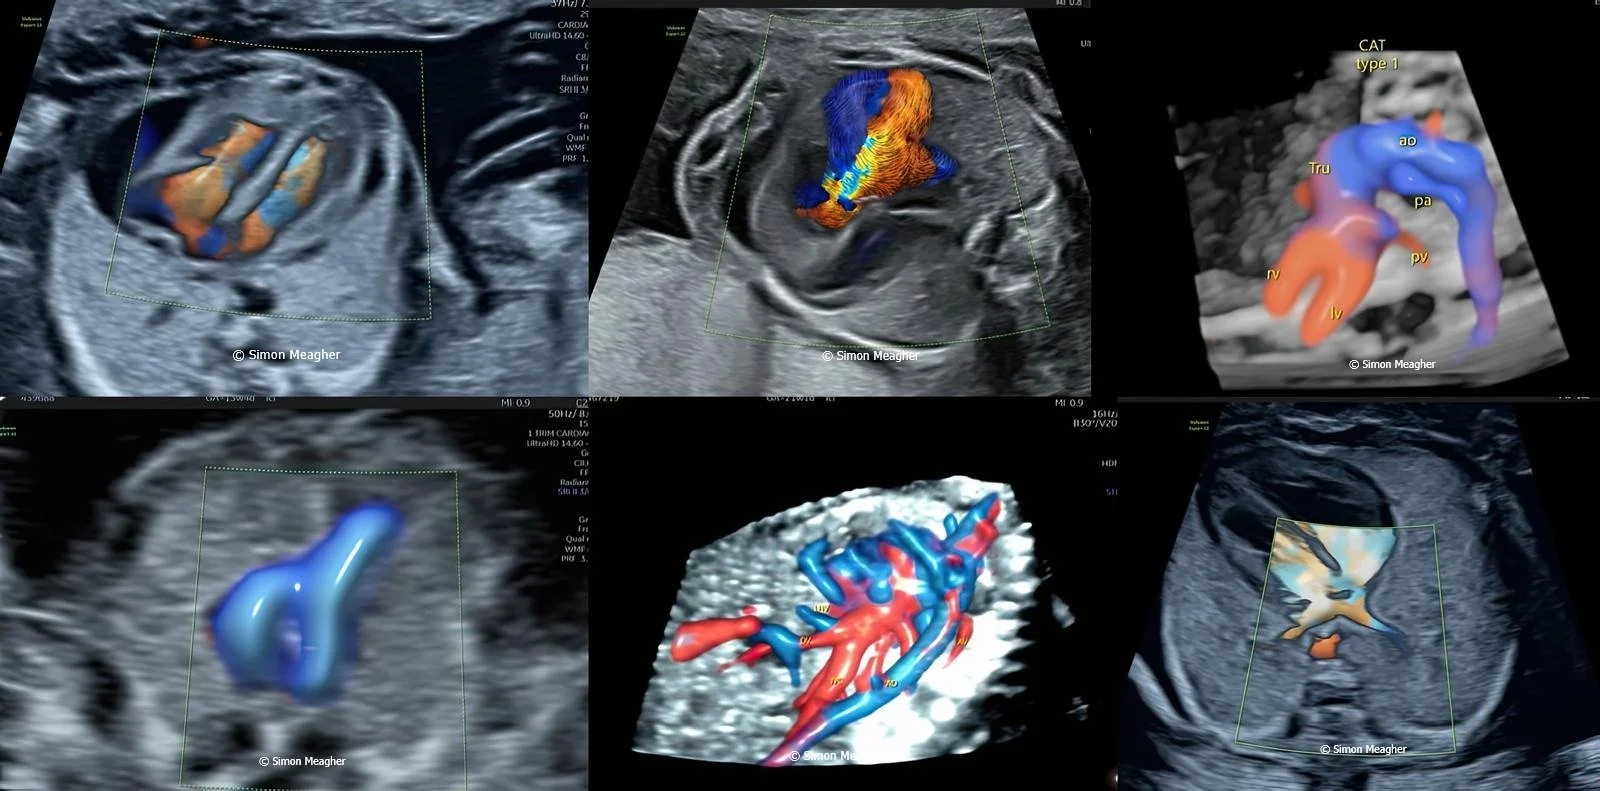

Join Professor Simon Meagher and leading experts for an intensive masterclass designed to transform your clinical practice.

This high-impact, one-day event delivers live scanning demonstrations, real-world case studies, and cutting-edge techniques across all trimesters.